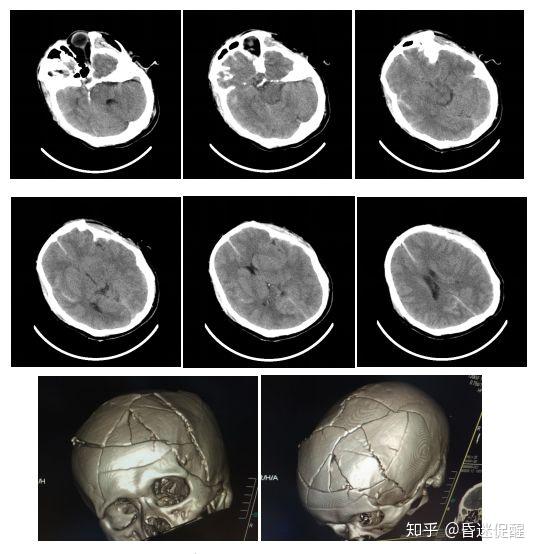

颅骨粉碎性骨折并上矢状窦损伤并硬膜外血肿并脑疝形成

轴索损伤,左侧额颞顶硬膜下少量出血,蛛网膜下腔出血,颅骨粉碎性骨折